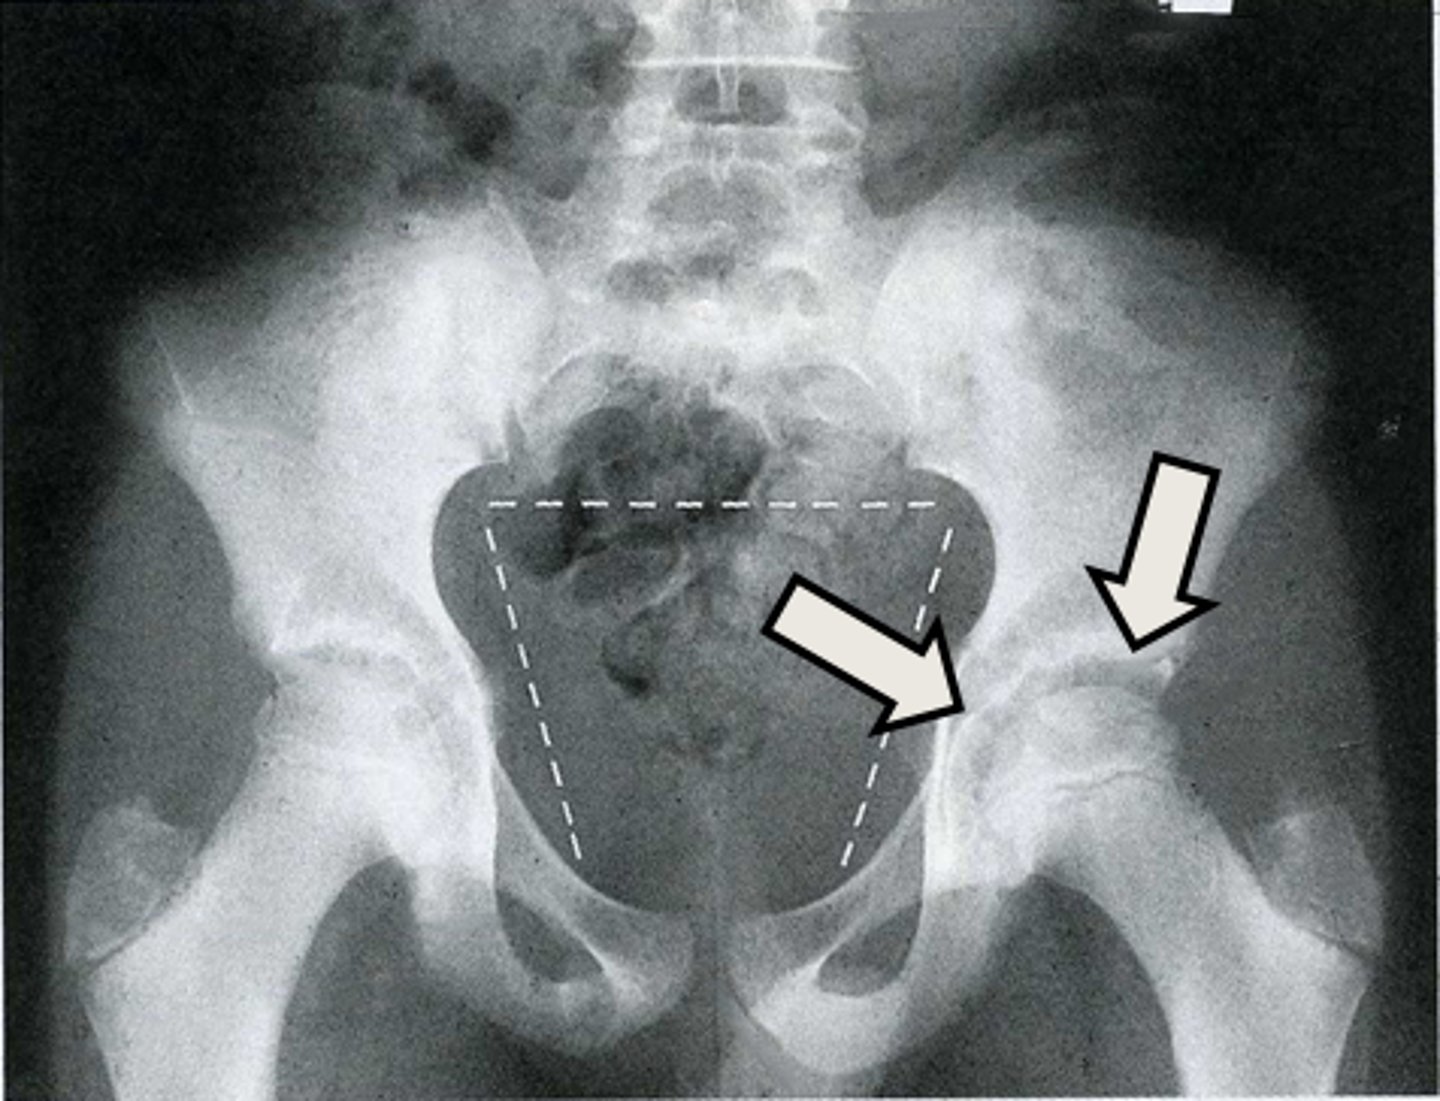

Axial male pelvis CT

What is the image?

78

Descending colon/sigmoid colon juncture

<p>What is indicated in the image?</p>

New cards

What is indicated in the image?

80

L gluteus muscle

82

L internal iliac artery

84

L sacroiliac joint

86

R gluteus muscle

88

Posterior aspect of right iliac bone

90

R sacroiliac joint

92